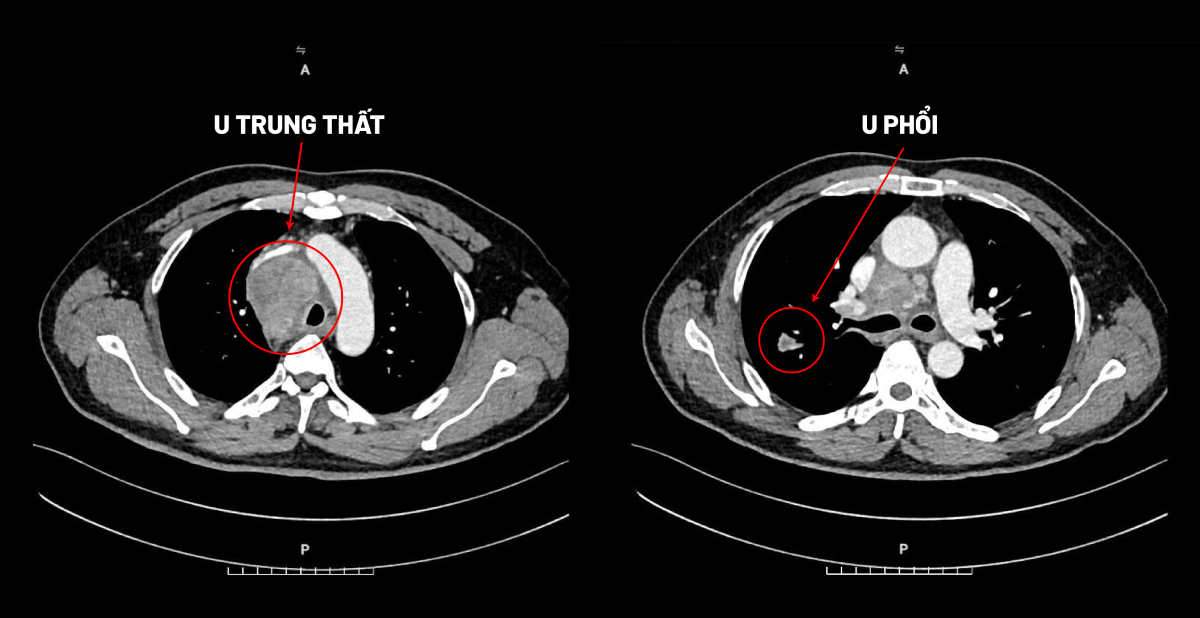

Kết quả chụp CT tại Bệnh viện Đa khoa Tâm Anh ghi nhận anh Yingjie, 51 tuổi, người Trung Quốc, có một khối u ở trung thất kích thước 45x53x65 mm xâm lấn tĩnh mạch chủ trên và một khối ở thùy trên phổi phải kích thước 12x10x14 mm.

Kết quả giải phẫu bệnh sau đó xác định cả hai khối u đều ác tính. Khối u trung thất là ung thư biểu mô tuyến ức và u phổi là ung thư biểu mô tuyến phổi.